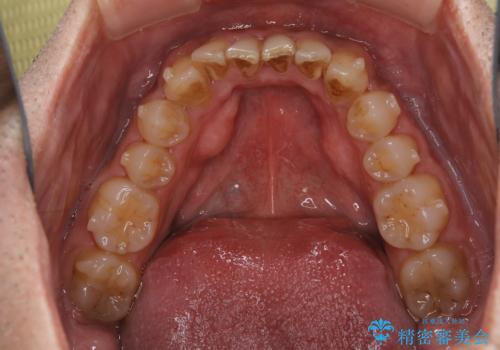

- インビザラインの治療中ですが、歯石やステインが気になるとのことでした。

コーヒーが大好きでよく飲むそうです。

全体的に歯石やステインが付着していたため、エアフロー60分コースを行いました。